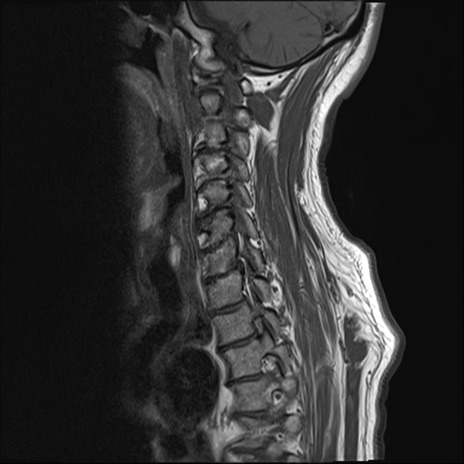

【整形】TIPS症例7 頚椎MRI T1WI(矢状断像)

頚椎MRI

矢状断像と横断像